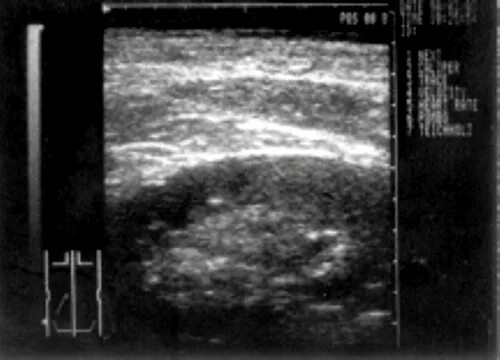

Узи аномалий